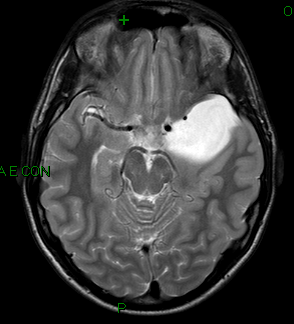

Da maggio 2011 Francesco, 15 anni, ha una sensazione di testa leggera, “vuota”, a sinistra associata a sensazione di fastidio a livello dell’occhio sinistro. Da una settimana si è aggiunto dolore all’orecchio omolaterale. Francesco ha già eseguito una valutazione ORL risultata normale. Giunto al nostro Ambulatorio di Neurologia Pediatrica a luglio 2011, rileviamo un esame obiettivo generale e neurologico normale. Eseguiamo anche l’EEG, che risulta normale. Prescriviamo inoltre, senza urgenza, un approfondimento tramite RM cerebrale. Considerata la necessità di rimuovere l’apparecchio odontoiatrico fisso e la scomparsa spontanea della sintomatologia, si decide di rimandare l’esecuzione della RM. Rivediamo il ragazzo a dicembre 2012: da un paio di mesi il quadro si è ripresentato, con le stesse caratteristiche, quindi Francesco ci porta in visione la risonanza che ha eseguito. L’indagine evidenzia una formazione compatibile con voluminosa cisti aracnoidea in sede temporale polare sinistra (5 x 3,5 x 3,5 cm) che disloca il lobo temporale omolaterale (Figura). ![]() La consulenza neurochirurgica conferma che i sintomi potrebbero essere legati a un’irritazione della dura madre della fossa cranica media sinistra; dato il quadro clinico-strumentale, il neurochirurgo consiglia intervento di fenestrazione della cisti e cisto-subaracnostomia. In attesa dell’intervento, Francesco è in preda alla disperazione… perché gli abbiamo detto che forse è meglio se lascia da parte il suo sport: la boxe. Discussione Le cisti aracnoidee (CA) sono raccolte liquorali circoscritte che si sviluppano tra la superficie cerebrale e la base o la volta cranica. Le CA sono più spesso sovratentoriali; di queste, il 70% circa si colloca nella fossa cerebrale media. Si tratta di un reperto frequente: su uno studio di 11.738 pazienti sottoposti a RM cerebrale di età pari o inferiore a 18 anni, la prevalenza di CA è risultata del 2,6%. Il riscontro è più frequente in età pediatrica (75% dei casi). La maggior parte delle CA è congenita, verosimilmente malformativa; raramente queste cisti rappresentano l’esito di traumi, infiammazioni o sanguinamenti che causano aderenze subaracnoidee. Le CA sono spesso asintomatiche; in questo caso il loro rinvenimento rappresenta un reperto occasionale. I sintomi sono variabili in base alle dimensioni della cisti, alla sede interessata e agli effetti compressivi sulle strutture contigue. I quadri più frequenti sono rappresentati da epilessia, pubertà precoce, idrocefalo ostruttivo. Si tratta di reperti di semplice riscontro alla RM o alla TC: appaiono come masse tondeggianti di densità analoga a quella del liquor; talvolta la densità appare differente per il possibile contenuto iper-proteico o emorragico. Dal punto di vista dell’evoluzione, in alcuni casi le CA rimangono stazionarie nel tempo, altre volte aumentano di dimensioni poiché dotate di attività secretoria propria o per lo sviluppo di meccanismi a valvola unidirezionale. Considerate le possibili complicanze dell’intervento, le più recenti evidenze della letteratura concordano sul riservare la terapia chirurgica ai pazienti con sintomi debilitanti, come cefalea e epilessia, ai pazienti con cisti che aumentano di dimensioni, o a quelli portatori di CA voluminose (> 3 cm di diametro) con effetto massa significativo, come nel nostro caso. Bibliografia di riferimento